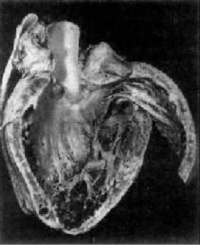

克山病(KD),亦称地方性心肌病(ECD),于1935年在中国黑龙江省克山县发现,因而命名克山病。70年代末急性克山病的发病率已由建国初期的52/10万下降到0.3/10万。1980年农村改革开放后,本病已戏剧性地消失了。在《静静的白桦林》中有所描述,还有部分人受此折磨。主要病变是心肌实质变性,坏死和纤维化交织在一起,心脏扩张,心室壁不增厚,附壁血栓常见,光镜下可见心肌变性坏死。电镜下可见线粒体肿胀,嵴分离和断裂。 克山病是一种流行于荒僻的山岳、高原及草原地带的以心肌病为主的疾病。用针掏背部的汗毛孔可见如类似羊毛的纤维。

克山病的主要病变是心肌实质的变性、

坏死和纤维化交织在一起心脏呈肌原性普遍扩张,心壁通常不增厚。20%的患者可见附壁血栓及肺、脑、肾、末梢血管的栓塞。光镜可见心肌变性和坏死。心肌变形呈弥漫性,坏死呈灶状分布。病变通常以左心室及室间隔部为重,右心室较轻。点镜主要表现为线粒性肿胀、增生和嵴及肌原纤维破坏。